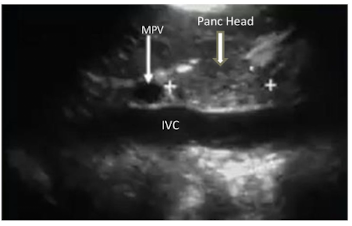

identify the sagittal image.

Red = ?

Blue = ?

Black = ?

Red = MPV

Blue = pancreatic Head

Black = IVC